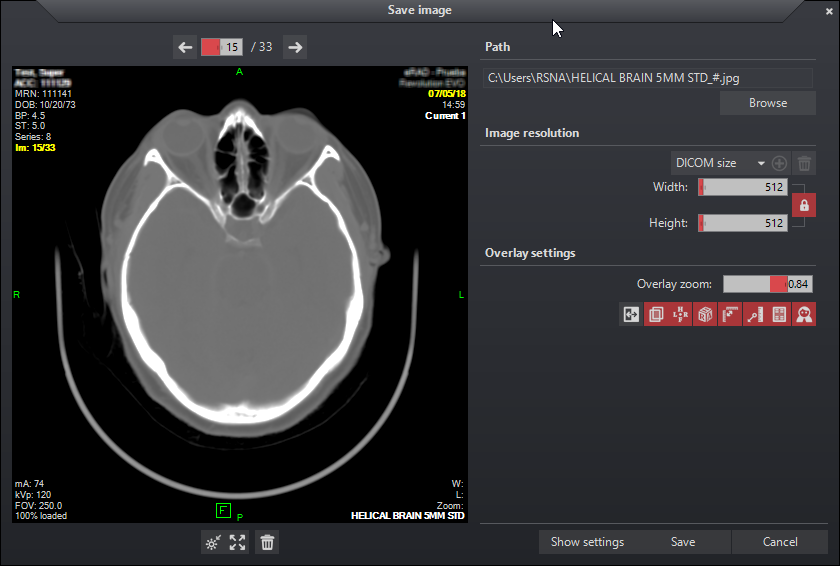

Save Image Panel

The save image panel is a staging area used to collect images before saving them to file. The save image panel provides tools for adjusting image characteristics just like in the main viewing workspace. Window level, zoom, and image pan changes can be applied to images within the preview panel using basic mouse functions.

Path

The user can specify a path for the files manually or by selecting the Browse button. The viewer supports five image formats: JPG, PNG, GIF, TIFF and BMP. The format can be selected from the drop down list on the file browser window or can be specified by adding a proper extension at the end of the file name in the path text field. If the filename doesn’t end in a valid extension, the user will be prompted when he clicks “Save” and will have the opportunity to either specify the desired format or to go with the default (JPEG).

Image resolution

Image resolution can be specified using the slider bars. The maximum resolution is 10000 pixels for each side. The current image ratio is locked by default and can be unlocked by clicking the lock button ![]() . When the ratio is locked, the sliders will move together in order to maintain the image aspect.

A drop down list containing predefined resolutions is available. DICOM size restores the image to the original size. The user may add and save new entries by first adjusting the slider bars then clicking the add button ![]() . Select a saved value then press the trash button

Overlay settings

Overlay information size can be changed by using the Overlay zoom slider bar.

Navigation tools are available above the preview panel. Use the arrows or slider bar to move through loaded images. Additionally, scrolling the mouse wheel will also navigate through loaded images.

Below the preview panel there are tools to reset image characteristics, and remove.

Export image settings can be accessed by clicking the Show settings button